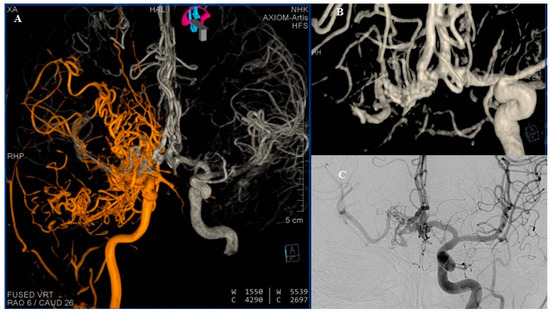

Figure 4. DSA (A) Reviewed representation of carotid circulations shown bilaterally after fusion of 3D reconstructions. (B) Three-dimensional reconstruction of the ACA complex showing double fenestration of the distal part of the left A1 segment and double fenestration of entire right A1 segment, where the capillary network is directly visualized. AComm and both A2 segments appear without anomaly. (C) The right MCA, better visualized through the contralateral carotid circulation. Many studies have reported a rare developmental anomaly which some authors refer to as “rete mirabile” or “rete-like collaterals” [2]. In 1968, Lie classified six types of collateral circulation resulting from developmental disturbances of the ICA. Type F in particular represents a mesh-like formation in the pre-cavernous segment, consisting of several small arteries that supply the cavernous segment [3,4]. The classic diagnostic criteria for rete formation include hypoplastic ICA, the presence of an arterial plexus between the internal maxillary artery and cavernous segment of the ICA, a dilated ophthalmic artery, a normal-sized supraclinoid segment of the ICA, supplied from both the arterial plexus and ophthalmic artery, bilateral lesions, and the absence of abnormal intradural blood vessels [5].